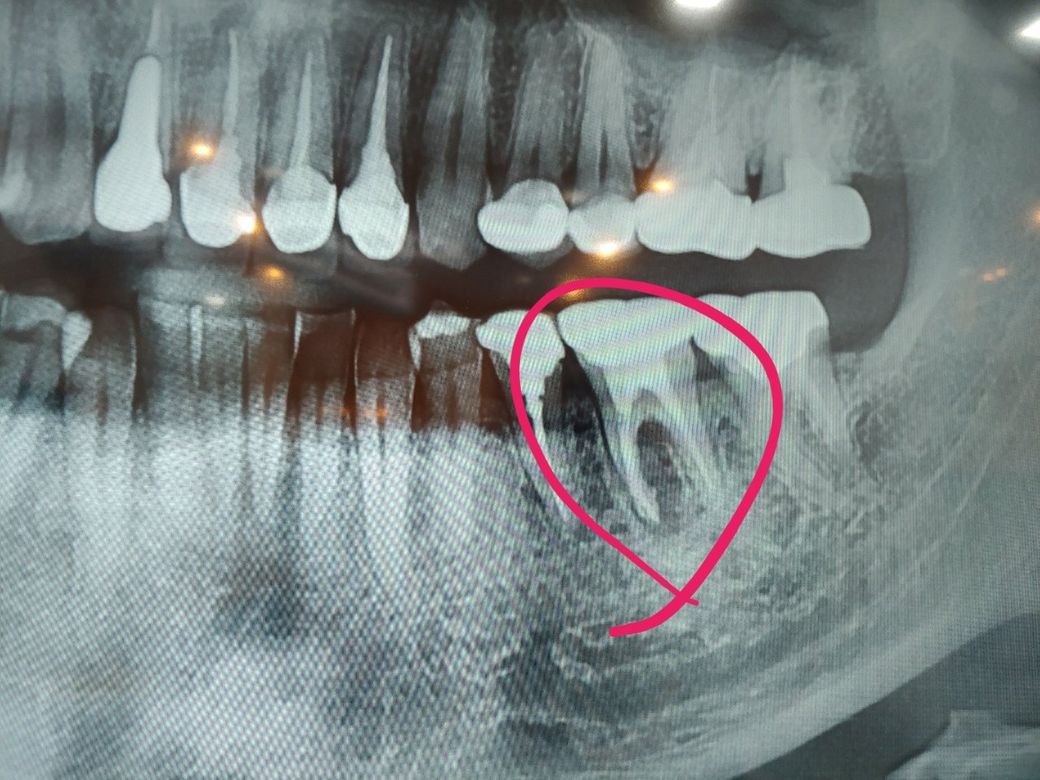

사진과 같은 J자형태의 골소실을 보이는 경우에는 치아의 파절의 가능성이 높습니다.

치아의 뿌리가 파절되었을 경우에는 재신경치료를 해도 얘후가 좋지 않아 발치후 임플란트를 하거나 금이간 뿌리만 제거하는 반측 절제술을 시행해 볼수 있습니다.

임상 사진을 보지 않더라도 현재 치아는 크랙이 의심되는 겅시 맞습니다. 치아 자체의 치조골 소실 정도로 보았을 때 크렉으로 인하여 나타났을 때 보이는 사진과 매우 흡사하다고 보시면 됩니다. 또한 이미 고름이 나오고 있다고 하셨으므로 이를 방치하게 되면 통증이 없더라도 해당 부위에 치조골이 계속 녹을 수 있어 추후 임플란트 시술을 어렵게 할 수 있습니다. 물론 재 신경치료 가능성도 있기는 하지만 크라운을 열고 신경치료 도중에 크랙이 관찰되면 더 이상 치료는 불가능하고 발치 이후 임플란트로 나아가야 합니다.

검정색이 J자형으로 나있는 경우

보통 크랙이라 진단합니다.

(검정색부분은 뼈가 잘 없다는 뜻입니다.)

치아 뿌리 2개중 앞의 뿌리 주위에 x ray 상에서 검게 보입니다.

이렇게 검게 보이는 이유는 치아 뿌리 주위에 염증(치근단 농양)이 있기 때문입니다.

염증의 크기도 꽤 크게 보이니 이정도의 치근단 농양이 있으면 치아 살리기 힘들고 발치하는 것이 권장됩니다.